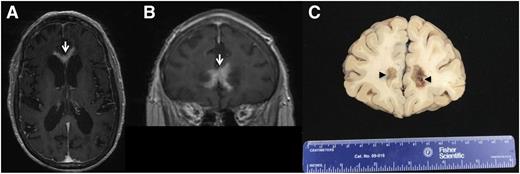

PCNSL is a highly infiltrative disease, particularly at relapse, whereupon the majority of lesions are multifocal and present at sites distinct from the focus of disease presentation. Histopathologic analysis of PCNSL supports at least 2 patterns of tumor dissemination. In one, an angiotropic growth pattern, lymphoma cells appear to coopt existing brain vasculature and migrate in the perivascular (Virchow-Robin) space. This invasive phenotype disrupts the blood-brain barrier and enables radiographic detection of lesions via pathologic contrast enhancement. A second pattern is direct invasion along nerve roots, such as the optic nerve, along white matter tracks such as corpus callosum, or into the meningeal space. (Figure 3). Common patterns of relapse occur within the vitreoretinal compartment and subependymal growth into the periventricular space, leading to spread within CSF pathways. (Figure 4).

PCNSL at relapse with periventricular and subependymal invasion. Common patterns of relapse are within the vitreoretinal compartment and subependymal growth into the periventricular space, leading to spread within CSF pathways. (A and B) T1 axial postgadolinium images of PCNSL that progressed after 3 cycles of HD-MTX: Contrast-enhancing disease is evident, involving the anterior commissure of the corpus callosum. (C) Brain autopsy, obtained 1 week after the MRI, confirmed periventricular DLBCL with subependymal spread.